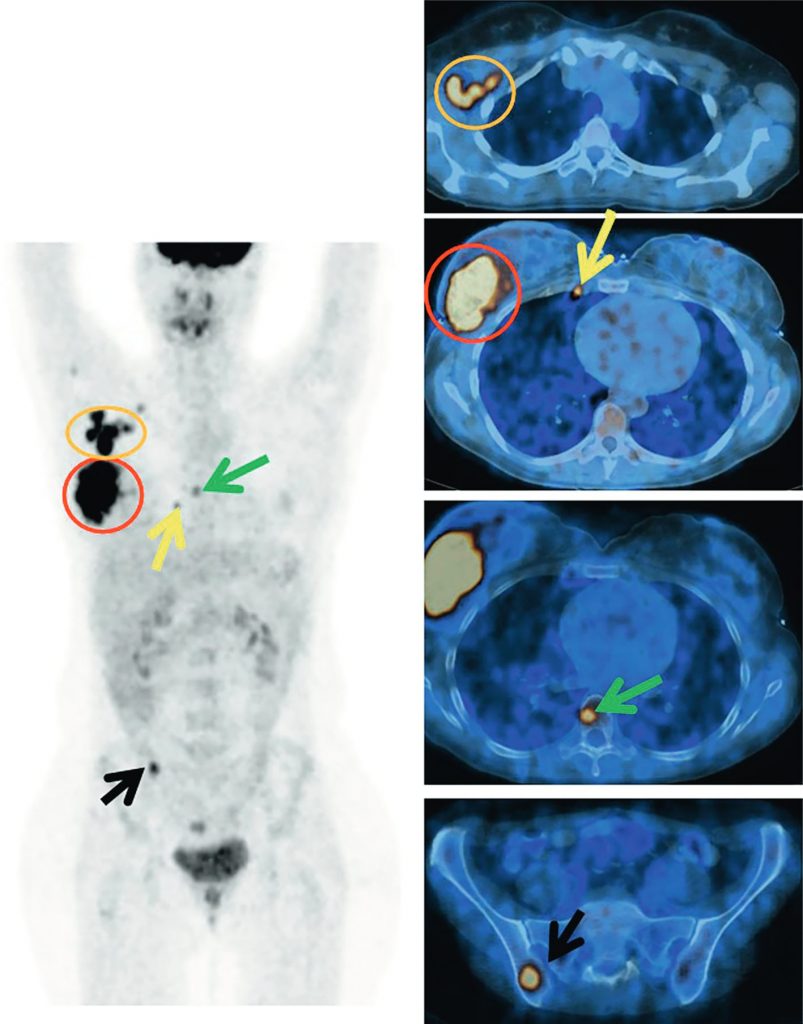

La TEP-TDM au 18FDG est recommandée dans le bilan initial des cancers du sein à partir du stade IIB (figure 34.2).

Fig. 34.2 Bilan d’extension par TEP-TDM au 18FDG d’un cancer du sein localement avancé.

Lésion mammaire (cernée en rouge) associée à une atteinte axillaire homolatérale (cernée en orange). Découverte d’une atteinte lymphatique mammaire interne droite (flèche jaune) ainsi que d’une atteinte osseuse : corps vertébral de T8 (flèche verte) et ischion droit (flèche noire).

Source : CERF, CNEBMN, 2022.